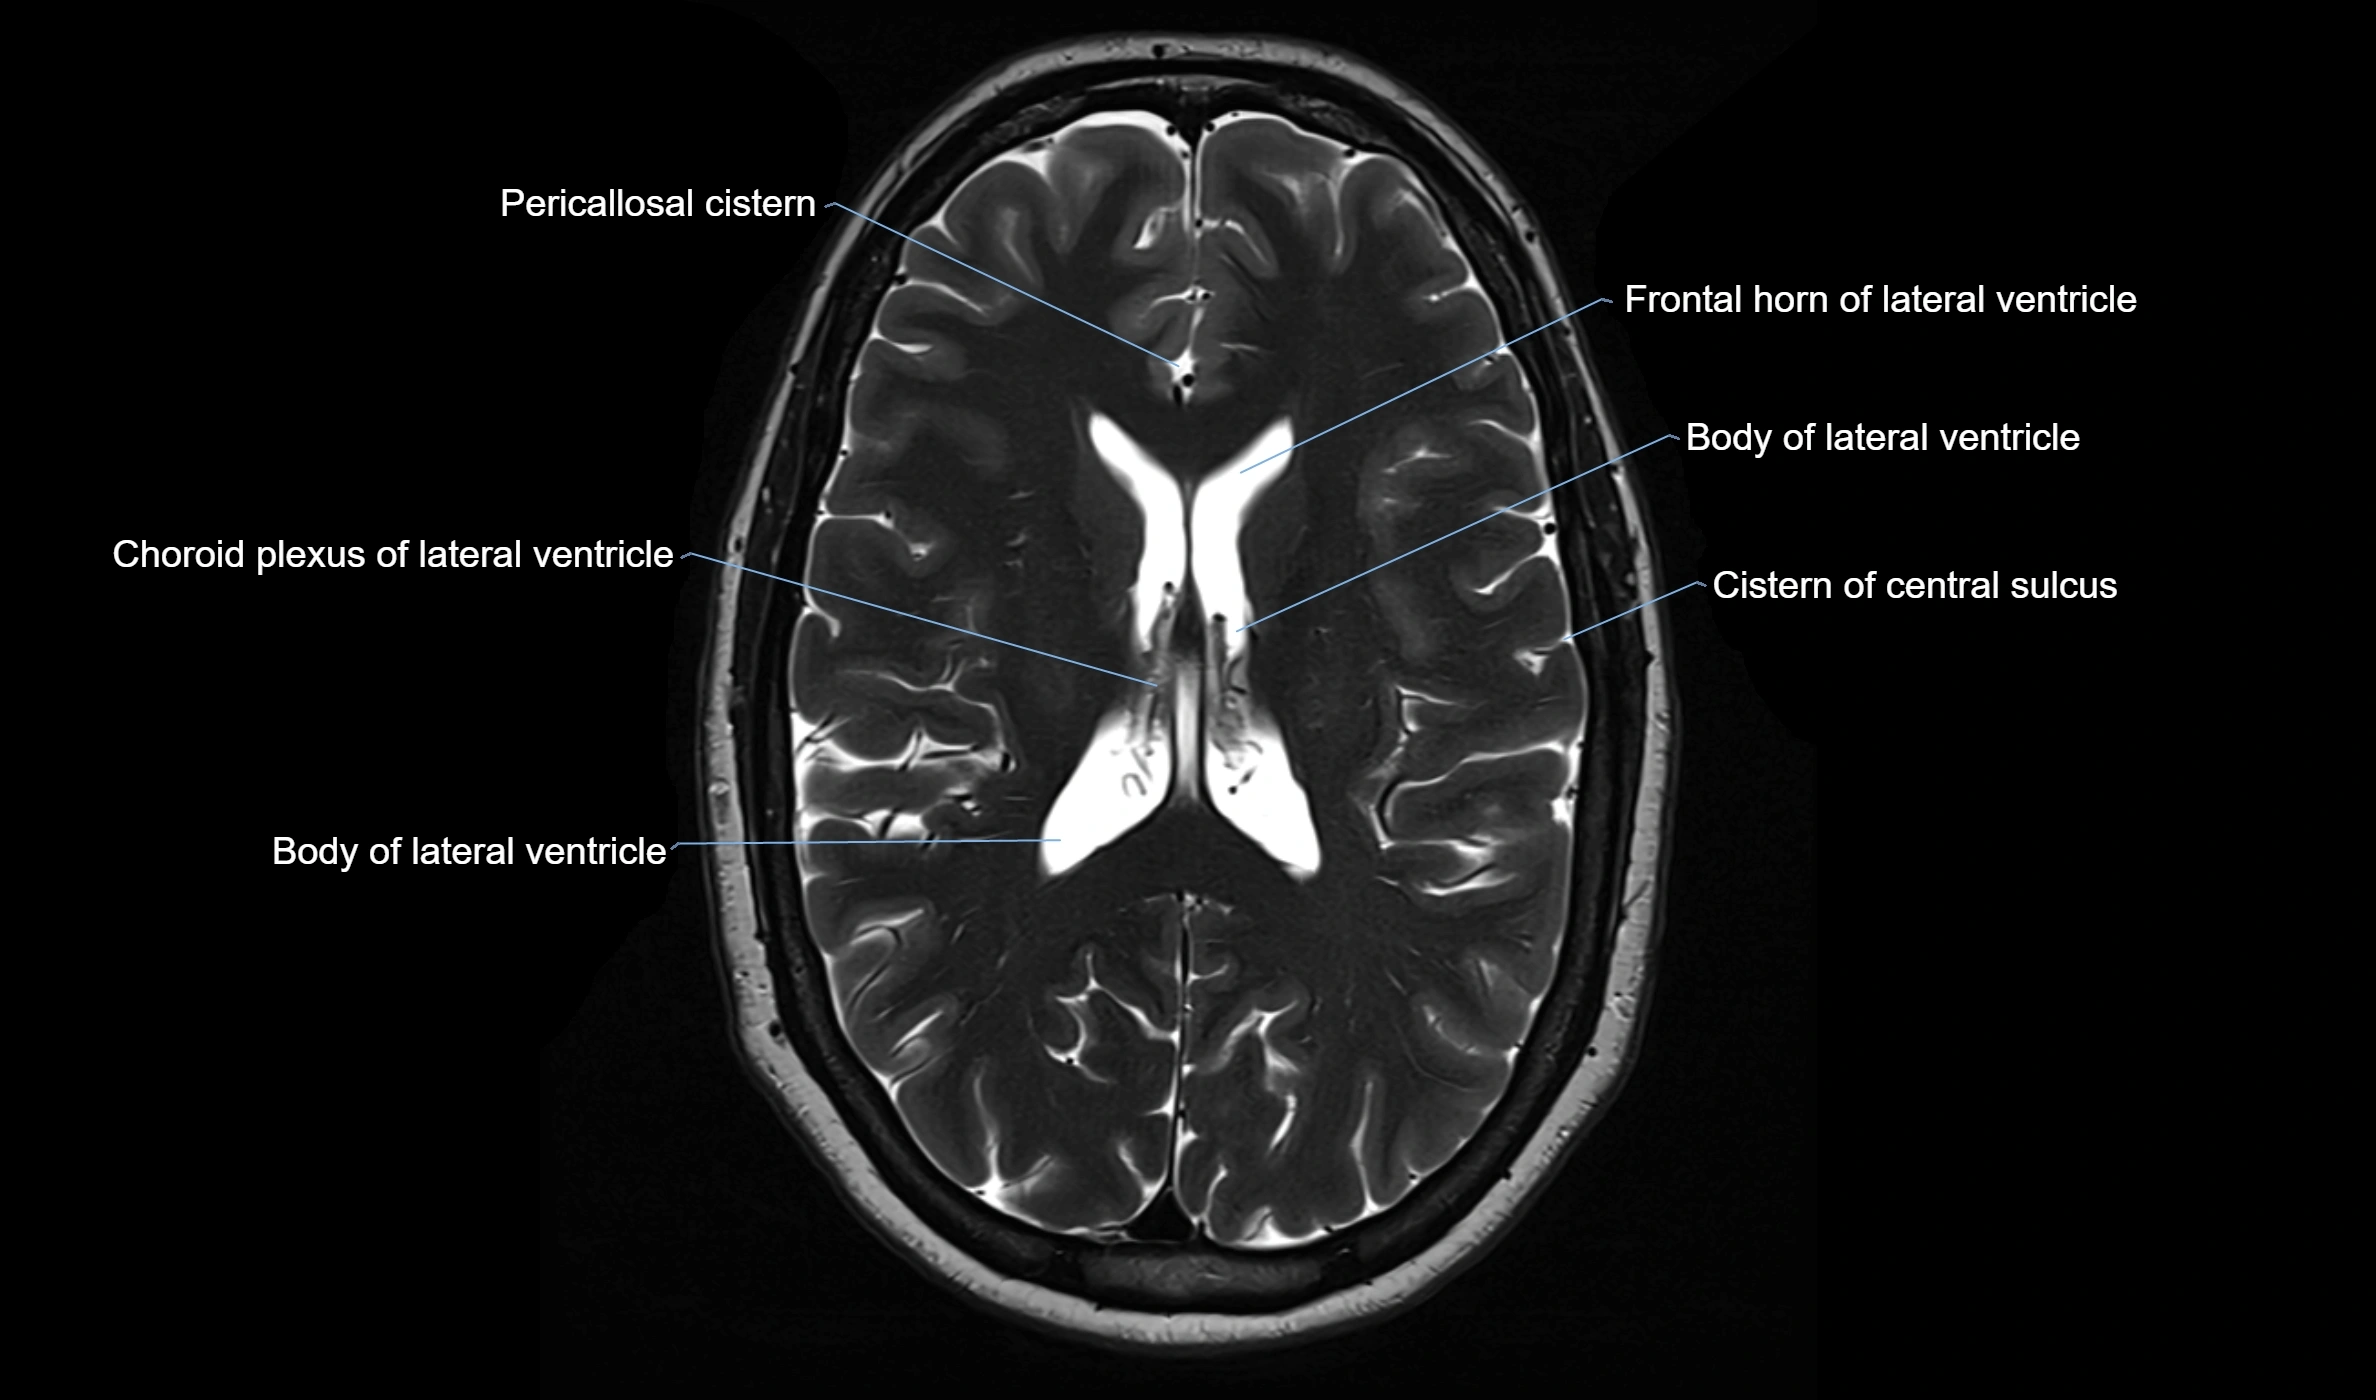

MRI images

image